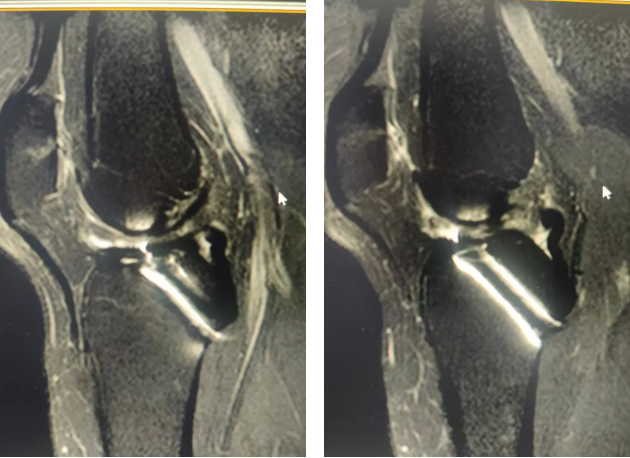

QQ截图20251015084006

术前膝关节MRI检查